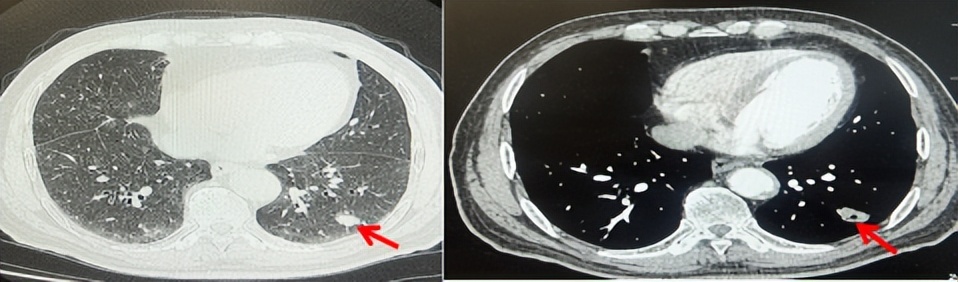

2024.09.12复查胸部CT示左侧胸膜结节,大者约为27mmx13mm,考虑转移可能性大,纵隔淋巴结增大,恶性?(如图6)。患者行胸膜穿刺活检取病理,结果示(胸膜)结合免疫组化,支持鳞状细胞癌,PD-L1(克隆号28-8)TPS约20%。分期为rT0N2bM1a IVA期,DFS为10个月。2024.09.24起行替雷利珠单抗联合紫杉醇+卡铂方案治疗4周期,复查胸CT评效SD(如图7)。后患者因脑梗塞停止治疗,于综合医院就诊,后未返院复查及治疗。

图6:患者胸膜及纵隔转移(2024.09)胸部CT肺窗及纵隔窗

图7:替雷利珠单抗联合白蛋白紫杉醇+卡铂治疗4周期后(2024.12)胸部CT肺窗及纵隔窗